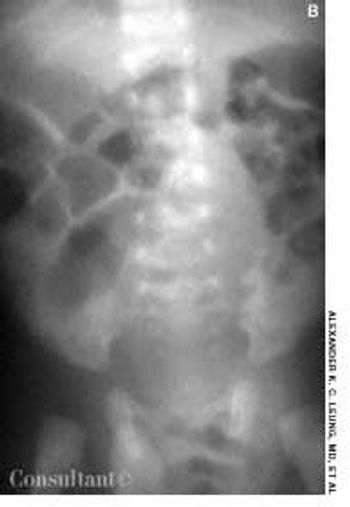

This condition involves the invagination of a proximal segment of bowel (the intussusceptum) into a more distal segment (the intussuscipiens). It occurs most frequently in infants between the ages of 5 and 12 months and is a leading cause of intestinal obstruction in children aged 2 months to 5 years. Intrauterine intussusception is associated with the development of intestinal atresia. The male to female ratio is approximately 3:2. Intussusception is slightly more common in white than in black children and is often seen in children with cystic fibrosis.

This disorder occurs in fetal development, when the midgut supplied by the superior mesenteric artery grows too rapidly to be accommodated in the abdominal cavity. Prolapse into the umbilical cord occurs around the sixth week of gestation. Between the tenth and eleventh weeks, the midgut retracts from its location at the exocelomic umbilical stalk back into the abdominal cavity. During this return, the midgut undergoes a 270-degree counterclockwise rotation about the axis of the superior mesenteric artery, followed by fixation to the posterior abdominal wall. Malrotation results from failure of the midgut to properly rotate and affix itself to this wall. This disorder occurs approximately once in 500 live births.